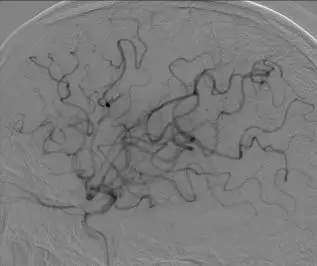

影像学表现与临床症状不匹配,发病超7小时。 DSA: 右侧颈内动脉C1段闭塞;右侧大脑中动脉M1段闭塞,颈外动脉经眼动脉向颅内代偿。

前交通动脉开放,同侧大脑前动脉通过软脑膜支代偿右侧大脑中动脉供血区域。

后循环通过软脑膜支及后交通动脉部分代偿右侧大脑中动脉供血区。